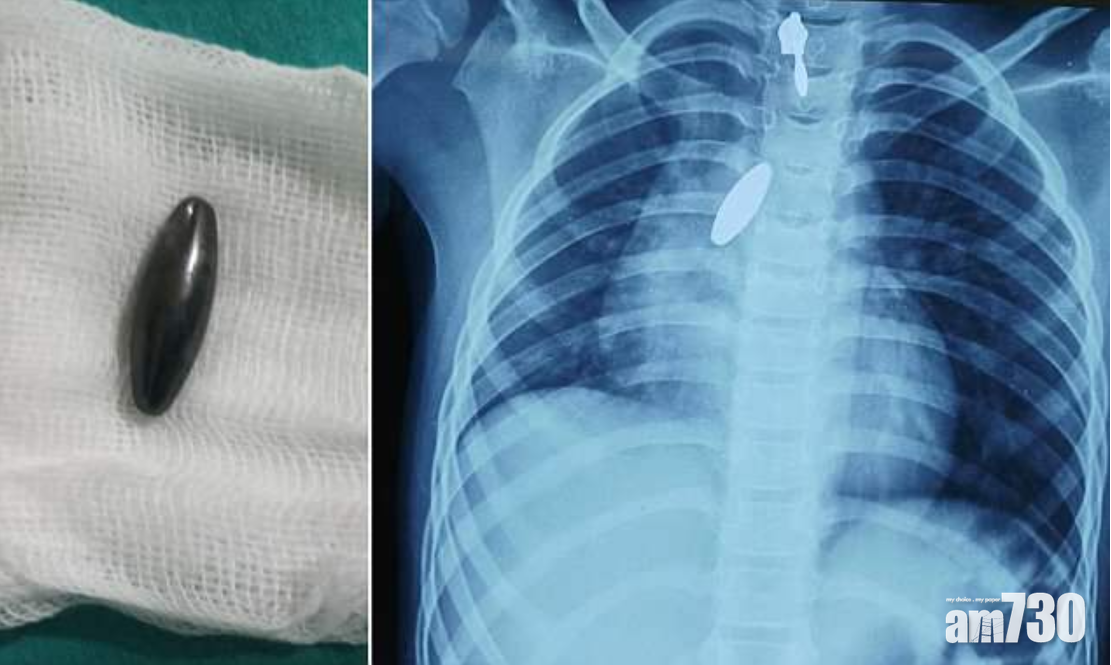

• 肺卡磁鐵 強力攝石吸出

肺卡磁鐵 強力攝石吸出

本地